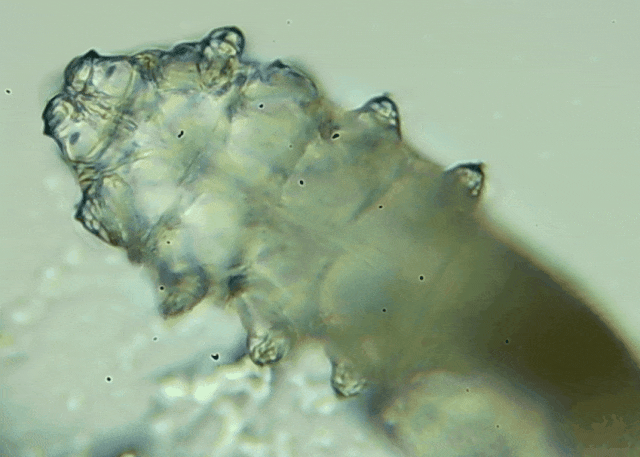

眼瞼位于眼球前面,分為上下眼瞼,而睫毛、一些腺體的開(kāi)口和淚小點(diǎn)都在眼瞼邊緣,也就是瞼緣上。蠕形螨是一種寄生于毛孔、腺管和瞼緣上的螨蟲(chóng),因?yàn)轶w型微小,肉眼無(wú)法察覺(jué)。...[詳細(xì)]